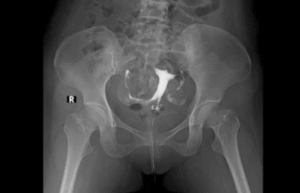

A Hysterosalpingogram (HSG) is a specialized X-ray procedure commonly used in fertility clinics to evaluate the structure and patency (openness) of a woman’s uterus and fallopian tubes. This diagnostic test plays a vital role in assessing fertility issues and determining potential causes of infertility, such as blocked fallopian tubes or uterine abnormalities.

The HSG test is performed using a contrast dye that outlines the inner shape of the uterus and fallopian tubes, allowing healthcare professionals to identify structural problems that may be interfering with conception. While the procedure is relatively quick, many women have concerns about HSG test pain, potential side effects, and what to expect during and after the test.

A Hysterosalpingogram (HSG) is a radiographic procedure that uses fluoroscopy (a continuous X-ray beam) and a radiopaque contrast dye to visualize the internal structure of the uterus and fallopian tubes. The dye, which contains iodine, is introduced into the uterine cavity through the cervix using a catheter. The purpose of the dye is to outline the shape of the uterine cavity and trace the patency of the fallopian tubes.

The HSG test involves fluoroscopic imaging to visualize the movement of the contrast dye through the reproductive organs. Real-time X-ray images are captured as the dye flows from the uterus through the fallopian tubes and potentially spills into the pelvic cavity, indicating tubal patency.

The contrast dye used in HSG tests is typically iodine-based because iodine absorbs X-rays well, appearing white on radiographic images. This high contrast allows for detailed visualization of the uterine cavity and fallopian tubes.